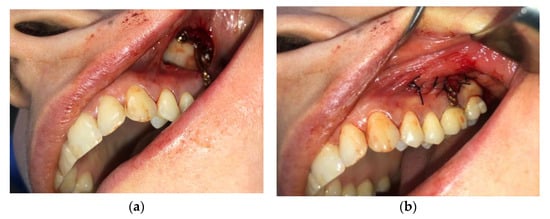

For this region, the same type of local nerve block was used. An incision was placed at the mucogingival junction starting from tooth 2.7 to tooth 2.3, followed by the elevation of the mucoperiosteal flap, with the exposure of the zygomaticomaxillary buttress (Figure 6). The plate was sterilized after personalization and before surgery. This preoperative step dramatically reduces surgery time and provides perfectly predictable results. The plate was anchored to the zygomaticomaxillary buttress using three 2.0 self-tapping screws. Nonresorbable 4/0 Supramid simple interrupted sutures were used, and these were then removed seven days after surgery.

Figure 6.

Zygomatic anchorage on the left maxillary buccal area: (a) with the exposure of the zygomaticomaxillary buttress; (b) Nonresorbable 4/0 Supramid simple interrupted suture.